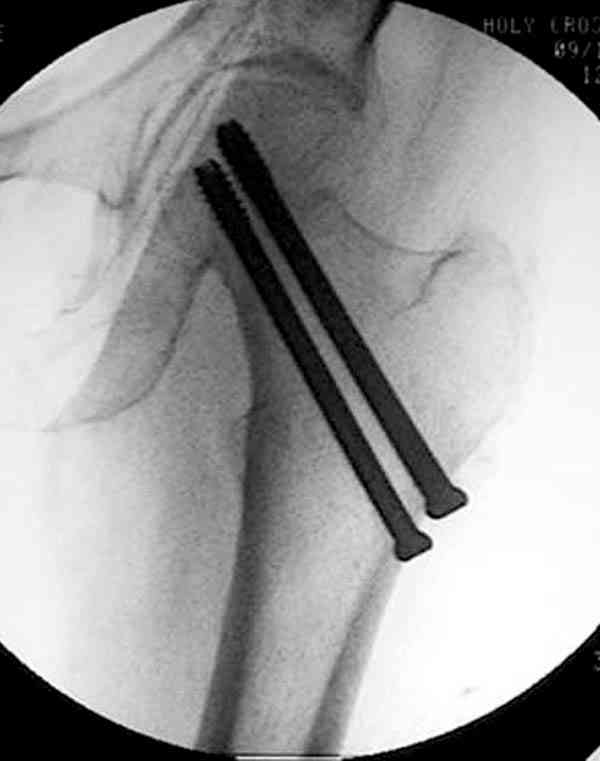

Коллега Челноков прав, здесь еще имеется риск перелома за счет ослабления латерального кортекса. Во время установки канюлированных шурупов за редким исключением спица вводится с одного раза, множественные попытки ослабляют латеральный кортекс, что станет источником перелома в этом месте.

В идеале для профилактики рефрактуры шурупы надо вводить не больше, чем под 130 градусным углом и не ниже уровня малого вертела.

Насчет биомеханических преимуществ одного шурупа  тоже возникает вопрос. Если придерживаться канонов механики, для перелома шейки необходимо 3 паралельных шурупа, расположенных ближе к кортикальному слою шейки.

Здесь случай перелома из-за ослабления латерального кортекса через 3 недели после операции на шейке. Шурупы были установлены под большим углом, слабый латеральный кортекс не выдержал нагрузку.